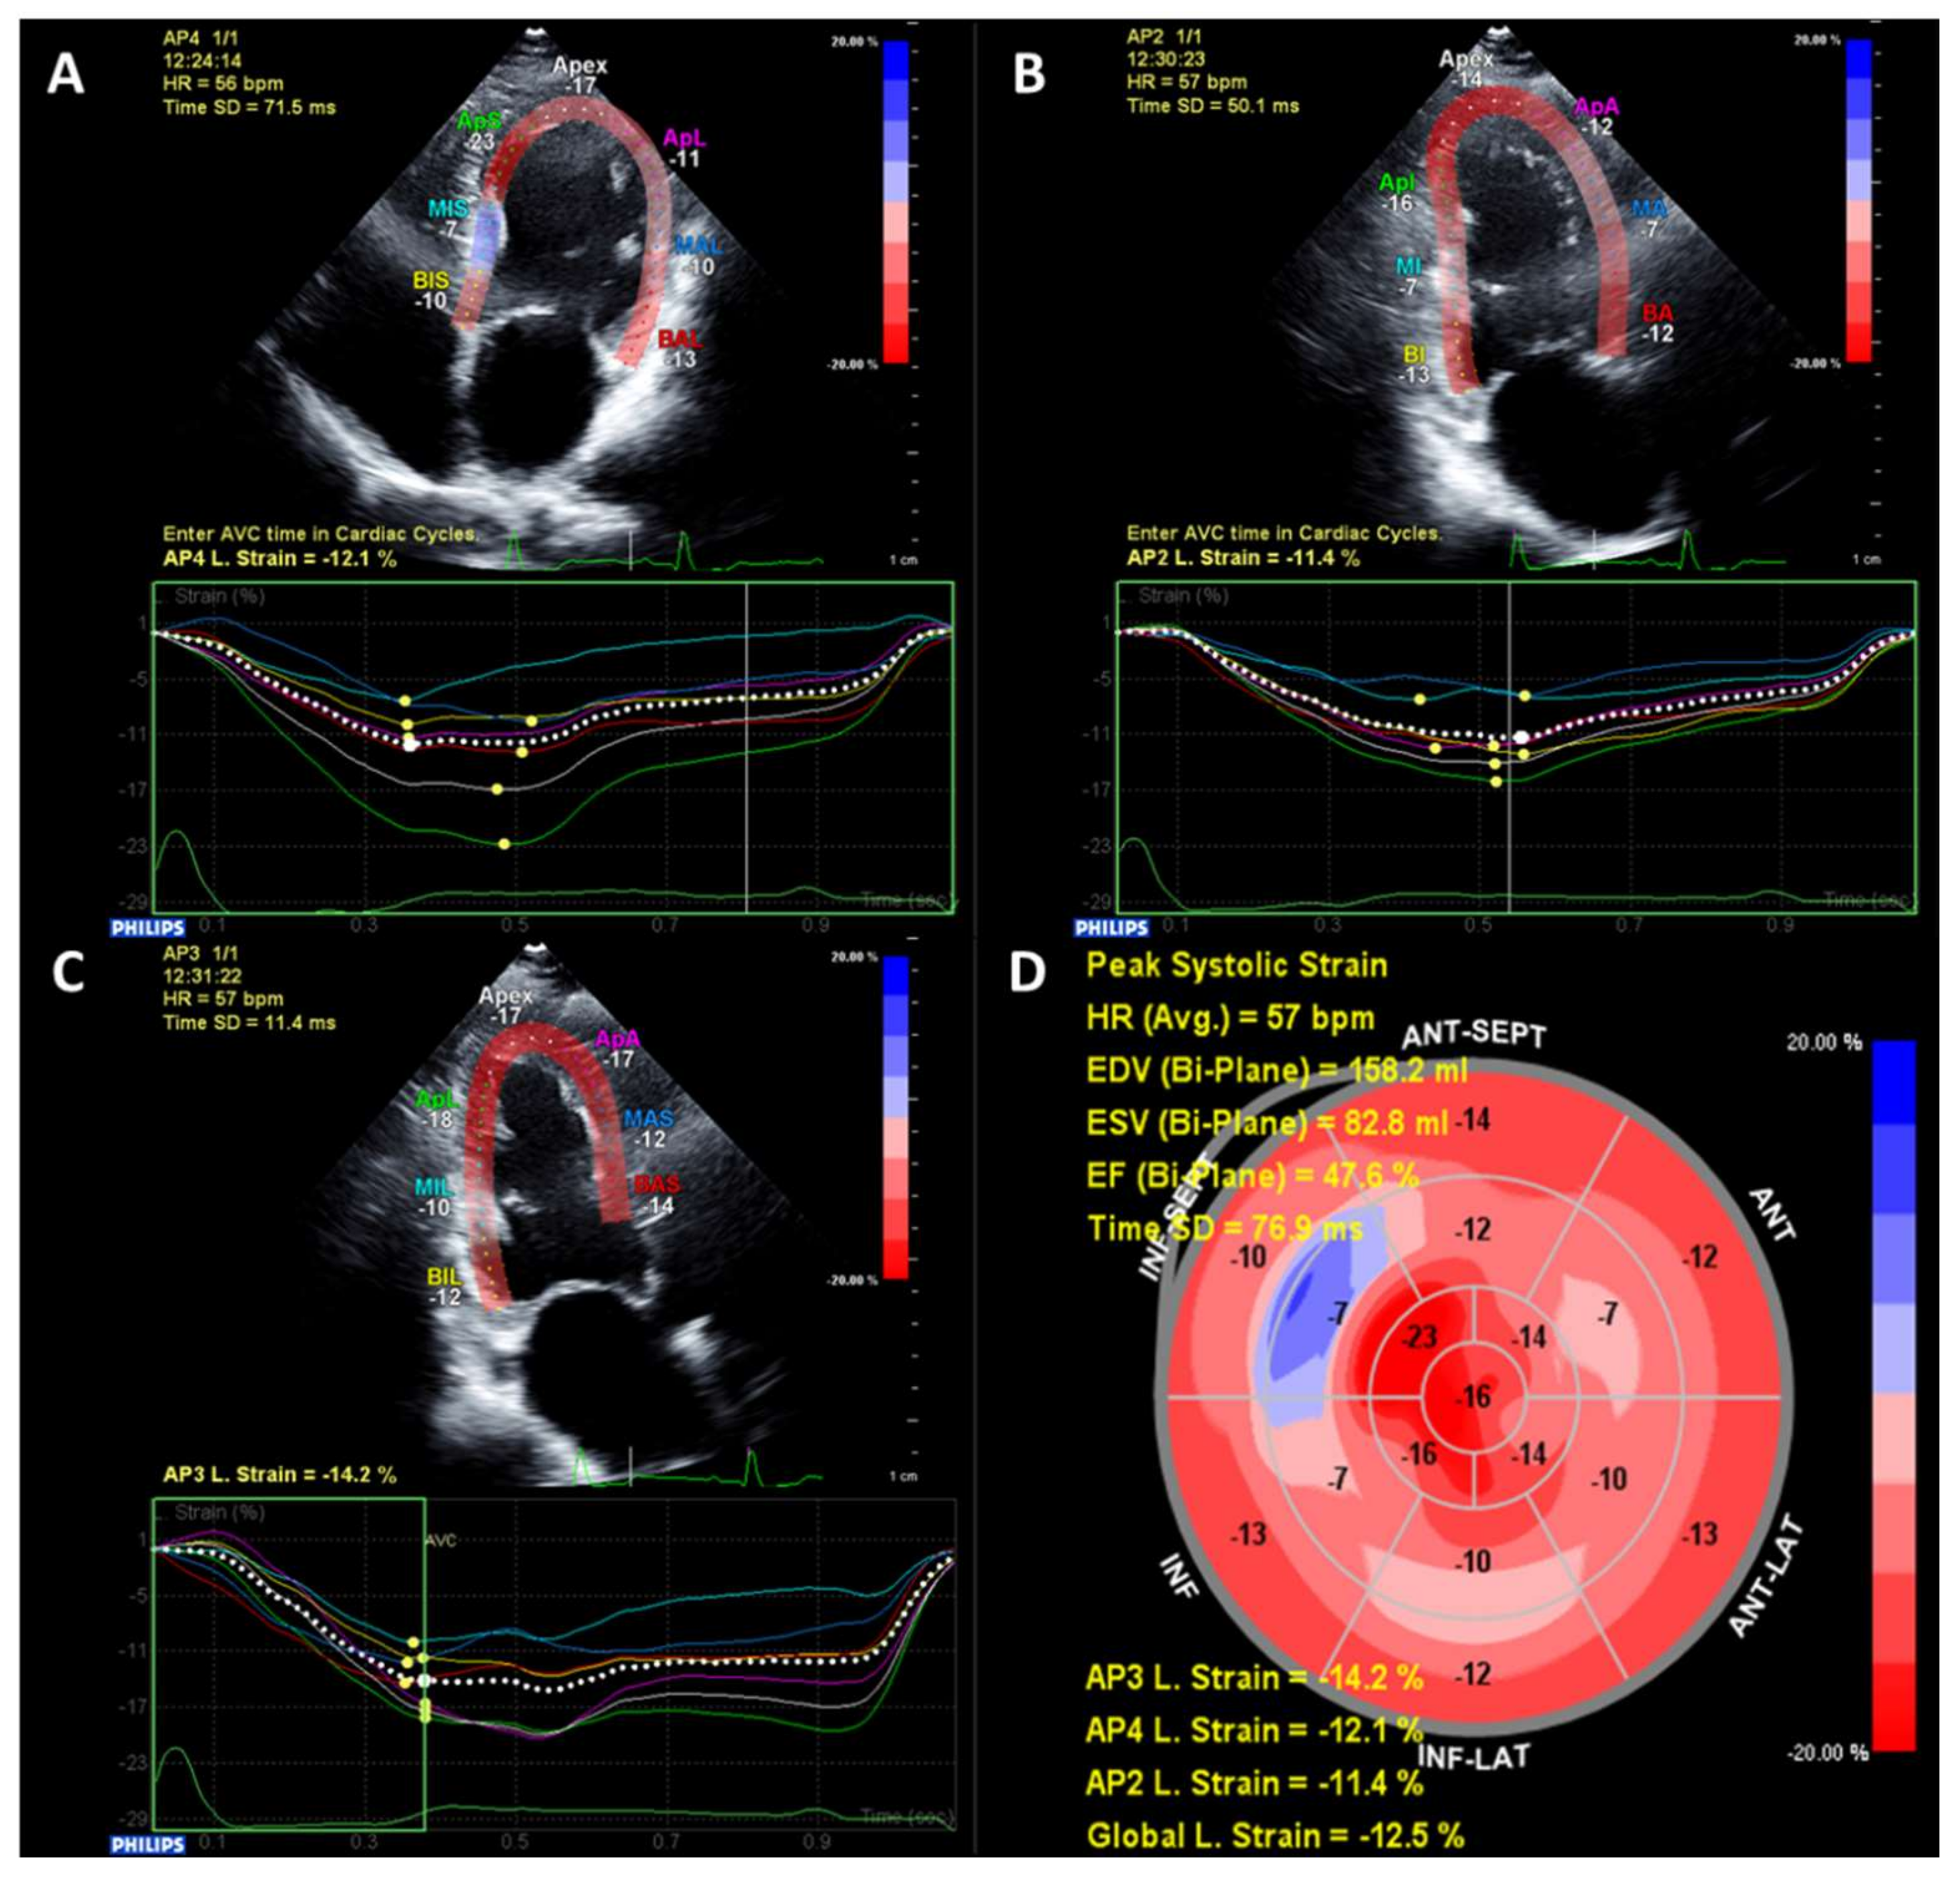

More recently, advanced echocardiography methods such as strain imaging using speckle-tracking have identified subclinical alterations in systolic myocardial function in patients with T2D and preserved LVEF (typically ≥50%) [22]. Strain is a measurement of myocardial deformation which is typically reported in three dimensions—longitudinal, circumferential and radial [23]. Strain is reported as a percentage change from diastole to systole, therefore due to the longitudinal and circumferential shortening of the myocardium lower values of longitudinal and circumferential strain represent better systolic function, whereas due to systolic myocardial thickening, higher values represent better systolic radial function. An example of strain imaging is shown in Figure 1. Global longitudinal strain (GLS) is the most studied parameter as it is more robust and reproducible, and also has independent, incremental risk prediction above and beyond ejection fraction [23,24]. GLS is frequently reduced even in T2D patients without overt structural heart disease compared to non-T2D patients [22]. Studies suggest that alterations in GLS may actually be a more sensitive marker of DCM than diastolic dysfunction [21].

Figure 1.

An example of echocardiographic speckle-tracking strain analysis. Images are taken in the apical 4-chamber (A), 2-chamber (B) and 3-chamber (C). A bullseye plot combining all three views is generated with reduced global longitudinal strain of −12.5% and reduced LVEF (47.6%) (D).